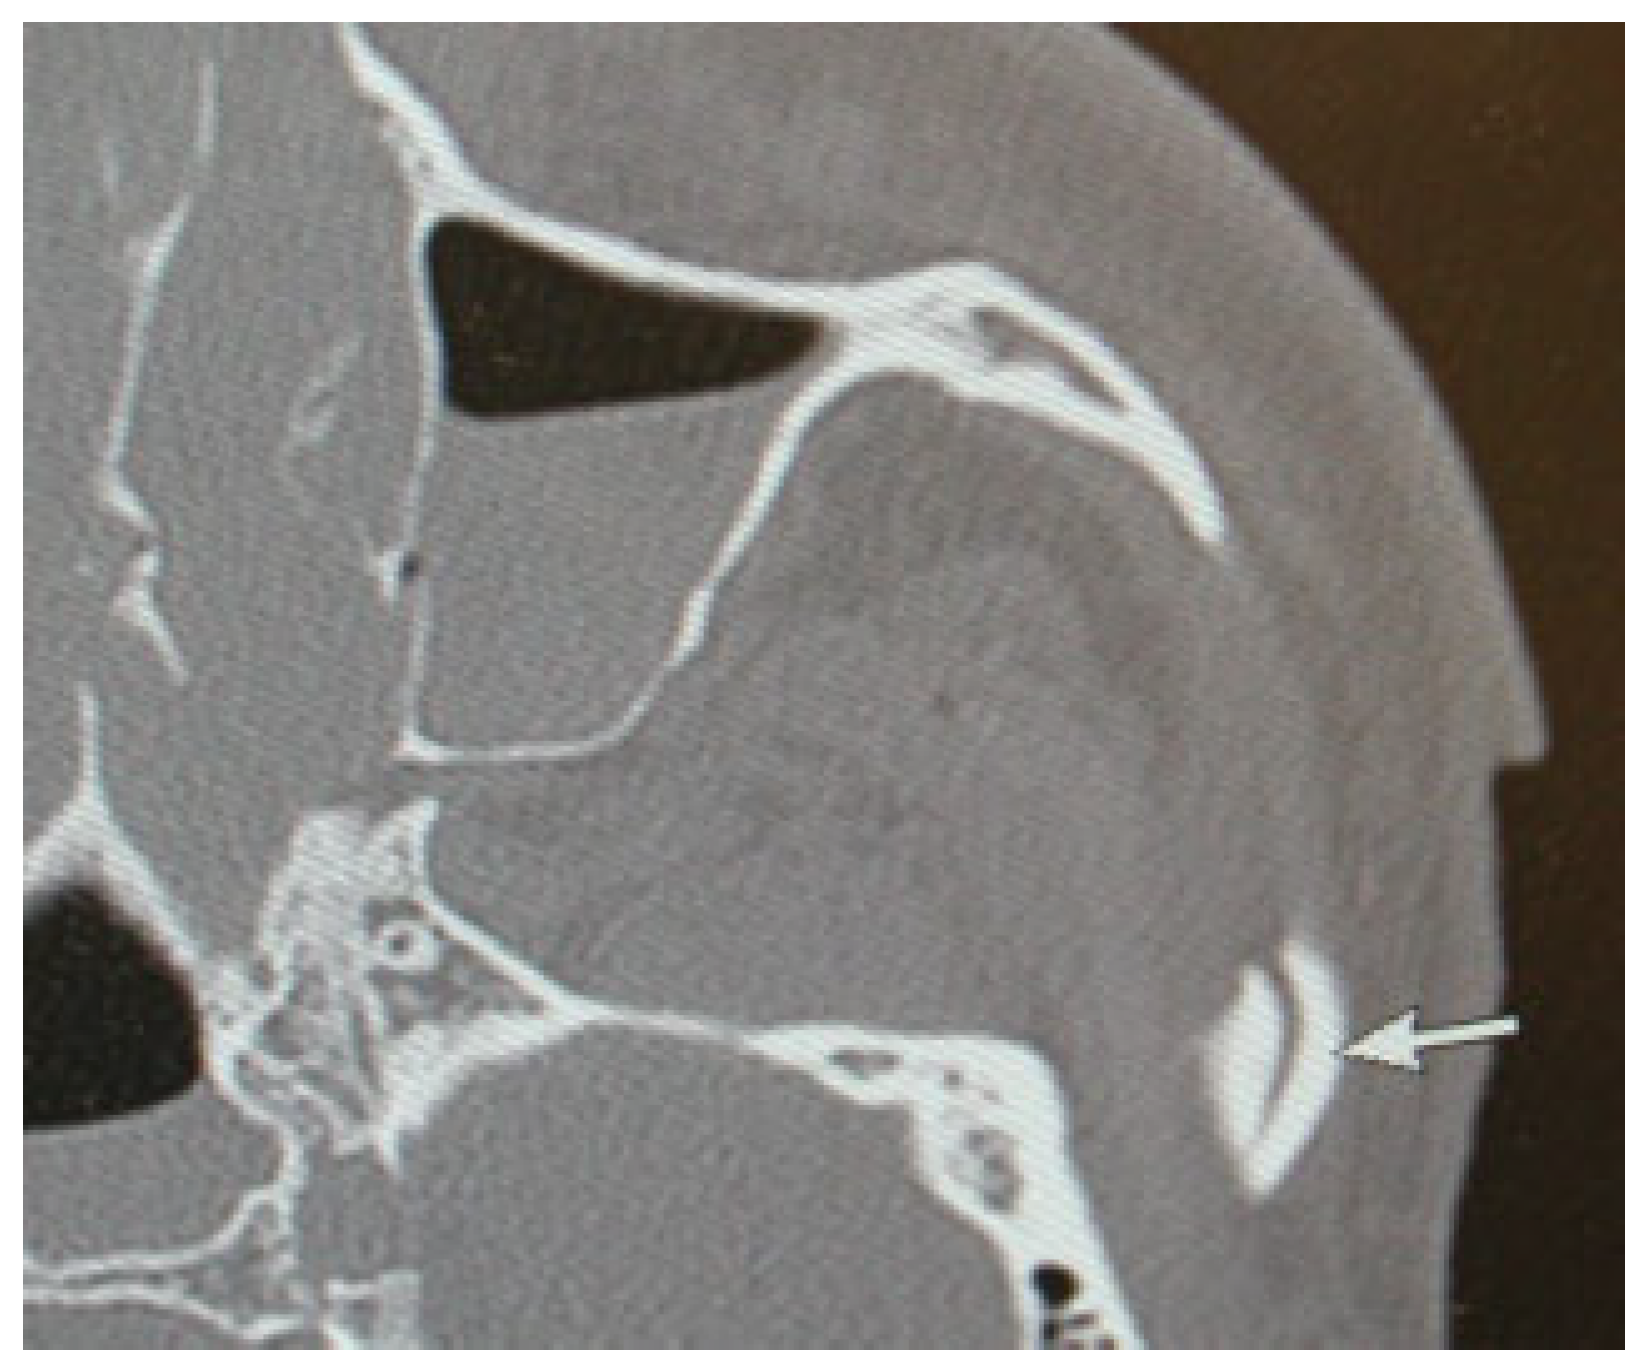

This coding system allows description of most relevant fracture patterns as illustrated in the case examples, such as LF fracture patterns as well as the differentiation between unilateral or bilateral fracture patterns. In a series of three case examples, we illustrate the coding of a fracture of the upper central midface (Figure 5); a bilateral LF I (LCM), LF II (ICM), nasal bone fractures (UCM), and a zygoma fracture on the left side (Figure 6); a zygoma fracture with lateral orbital wall involvement (Figure 7); and a fracture of the origin of the zygomatic arch (Figure 4). A range of additional fracture patterns are presented in a special case appendix [7] as electronic supplement to this issue of the Journal at www. aocmf.org/classification.

Figure 4. Fracture of the origin of the zygomatic arch. CT scan axial view showing a fracture of the origin of the zygomatic arch, passing through the temporal bony base of the glenoid fossa (arrow) that is added to the zygomatic region.